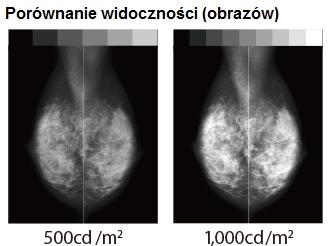

Zwiększona efektywność diagnostyczna

Monitor MS55i2 plus jest fabrycznie kalibrowany do jasności 1000 cd / m2, co czyni go najlepszym rozwiązaniem do obrazowania tomosyntezy piersi. Wysoka jasność ekranu monitora radykalnie zwiększa ilość widzianych odcieni szarości, dzięki czemu wykrywalność mikrozwapnień i guzów jest dużo większa.